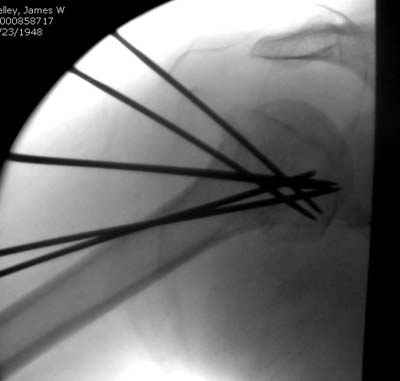

Женя, а как ты водишь спицы, в смысле, как делаешь входное отверстие, и как в него проводишь V-спицу? А то о дна из спиц, та, у которой не дошла до головки одна палочка буквы V, как-то выглядит на рентгенограмме, как будто или через очень большое отверстие введена, или каждая половинка через отдельные отверстия.

В чем ты видишь причину вторичного смещения?

Мне кажется, проблема в том, что не все концы спиц зашли в головку, и зашедшие - недостаточно далеко прошли.

Спицы провожу по передней и задней поверхностям плечевой кости через 4,5 мм отверстия на разных уровнях.

Уточни - обе части буквы V вводишь в одно отверстие? А то по снимкам выглядит, что в разные.

V-спица проводится через 4,5 мм отверстие. Видимо, из-за разной длины вторая половина спицы *пролетела* мимо отверстия, что и привело к вторичному смещению костных фрагментов.